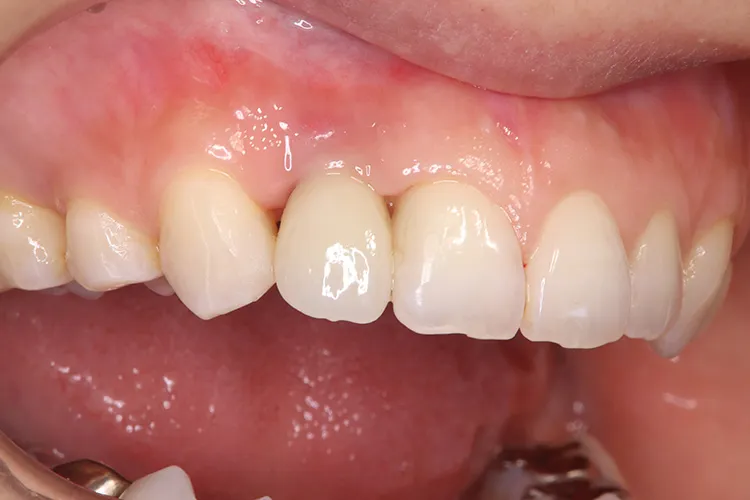

第一大臼歯1歯欠損をインプラントで回復したケースです。第一大臼歯は永久歯の中で一番最初に生える歯ですが、一番早く傷んでしまう歯でもあります。噛む力の60%を負担し噛み合わせの安定に大きく影響しますので、この歯が欠損すると噛み合わせに悪い影響を与えてしまいます。インプラントで治すことにより噛み合わせが安定するだけでなく、ブリッジのように隣在歯を削らないので天然歯の寿命を延ばすメリットもあります。